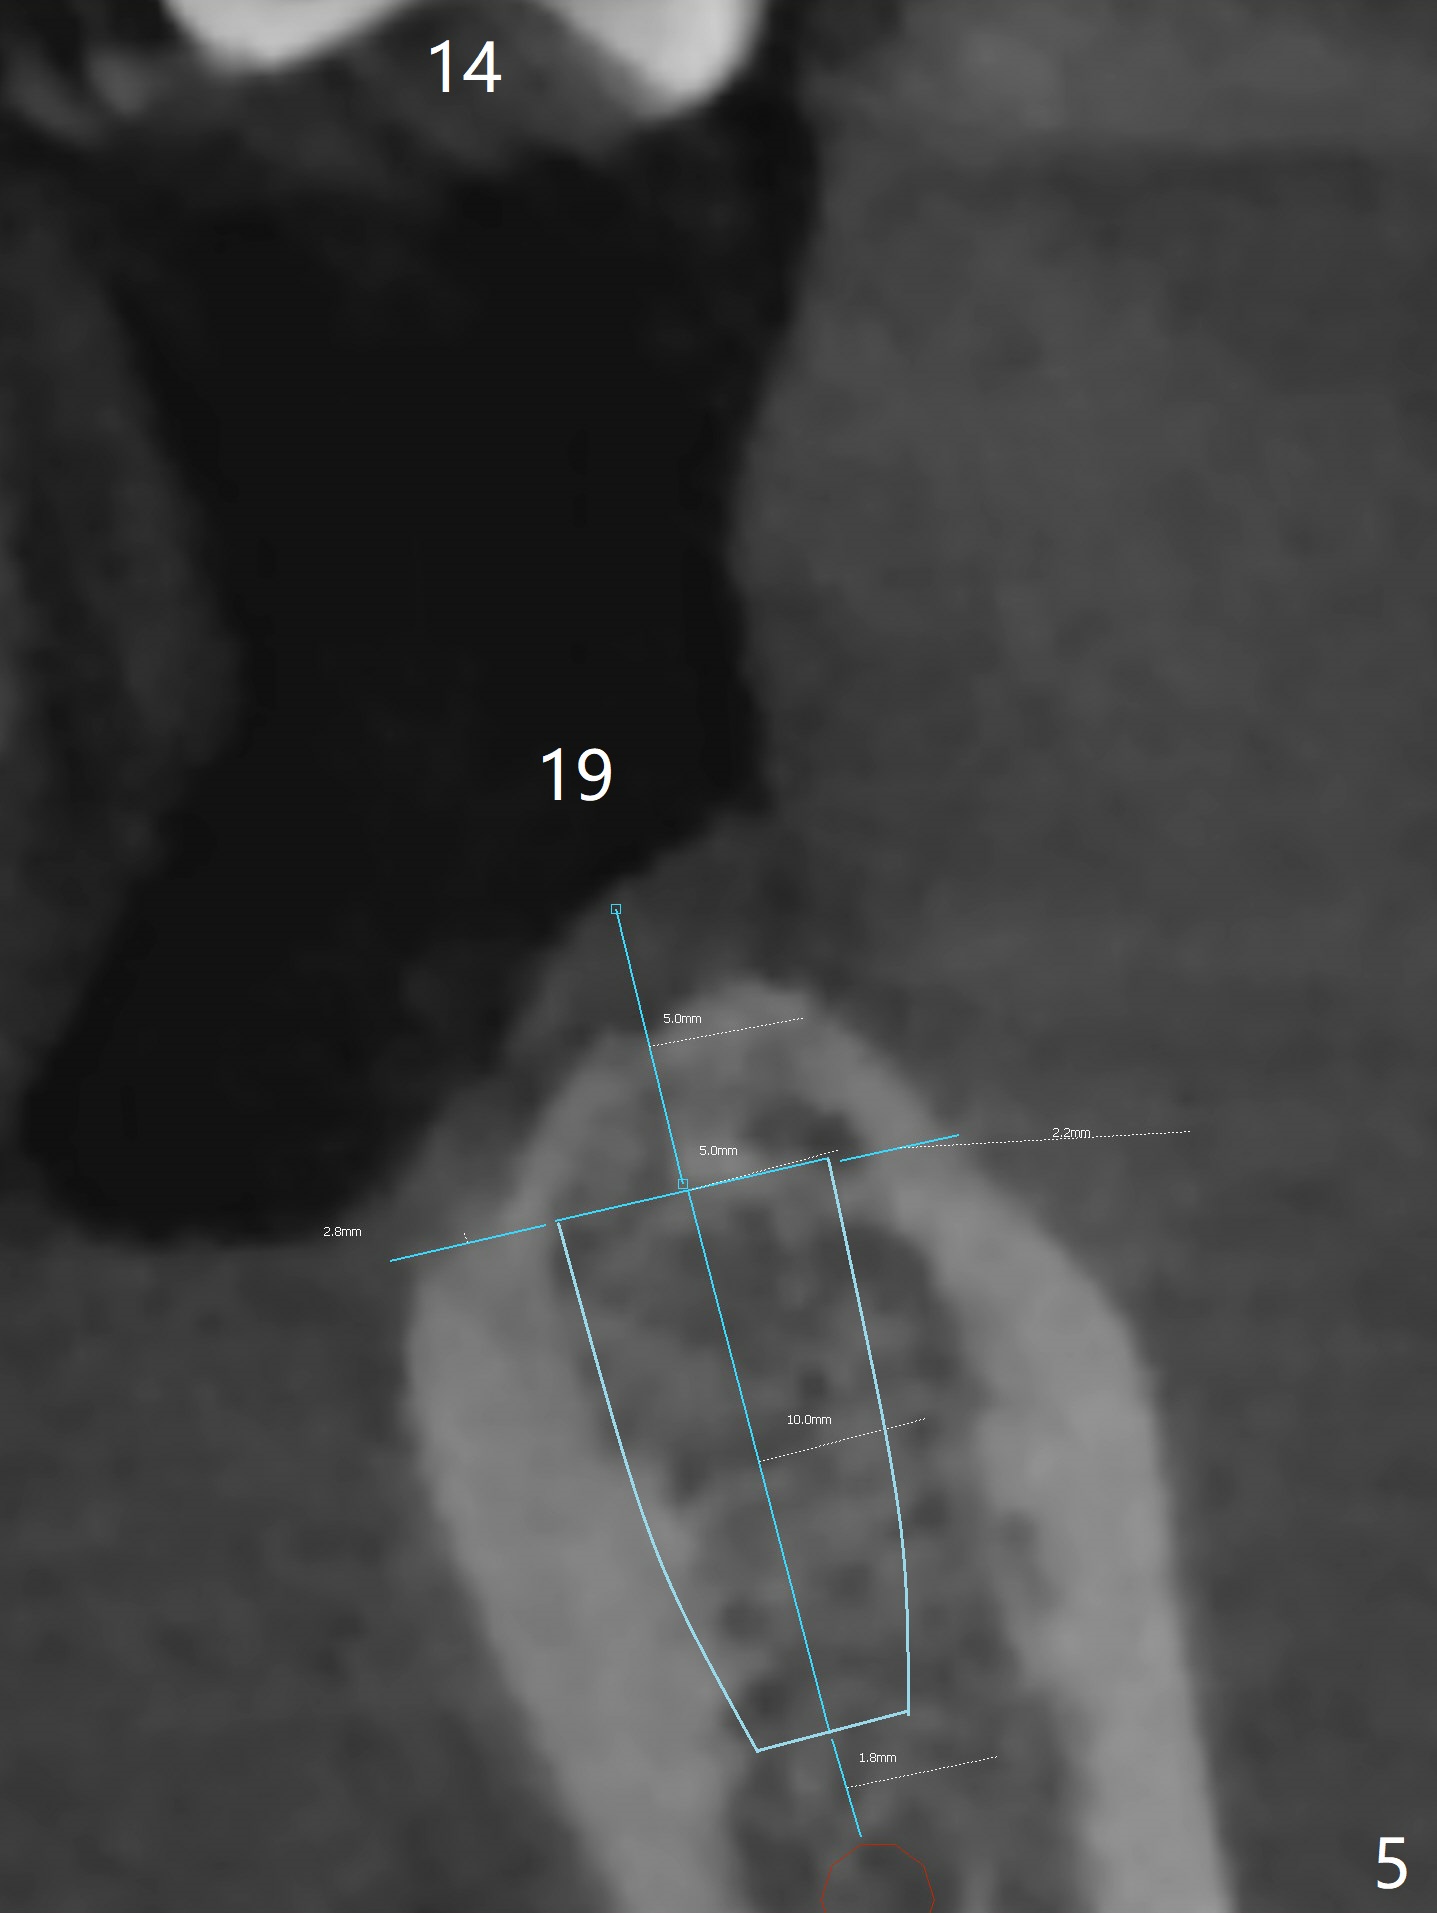

A 54-year-old man has poor dentition, including missing tooth of #19 and residual root at #20 (Fig.1). The lingual crest (Fig.2 (lingual view), Fig.4 (L)) is lower than the buccal one. The Inferior Alveolar Canal (Fig.3 IAC) becomes the Incisive Canal (IC, Fig.4 red circle) after the Mental Loop (Foramen). An implant at #21 will be placed at the level between the buccal and lingual crests (Fig.4) with osteotomy initiated in the middle of the socket. Bone graft is to be placed around the coronal end of the implant (yellow circles).

The socket at #19 appears to have not completely ossified (Fig.1 *, Fig.5). Use Magic Split and Magic Expanders to expand the ridge top so that an implant will be placed higher for favorable crown/implant ratio (reduce abutment screw loosening). Note the concavity at the site of #19 while osteotomy (Fig.2 *).